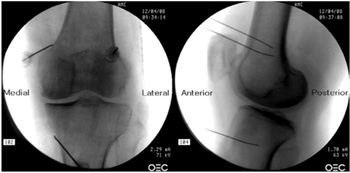

16. Kim DH, Lee MS, Lee S, Yoon SH, Shin JW, Choi SS. A prospective randomized comparison of the efficacy of ultrasound- vs fluoroscopy- guided genicular nerve block for chronic knee osteoarthritis. Pain Physician. 2019;22(2):139-46.

25. El-Hakeim EH, Elawamy A, Kamel EZ, Goma SH, Gamal RM, Ghandour AM, et al. Fluoroscopic guided radiofrequency of genicular nerves for pain alleviation in chronic knee osteoarthritis: A single-blind randomized controlled trial. Pain Physician. 2018;21(2):169-77.